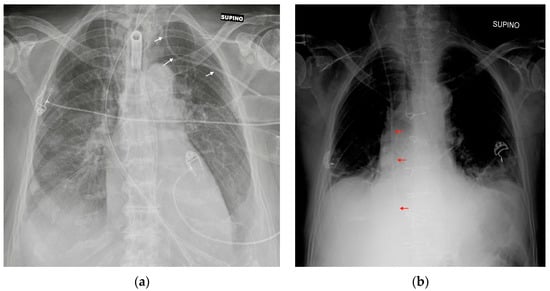

4. Airway Devices

4.1. Endotracheal Tubes

6.1. Nasogastric Tubes

6.2. Nasoenteric Tubes